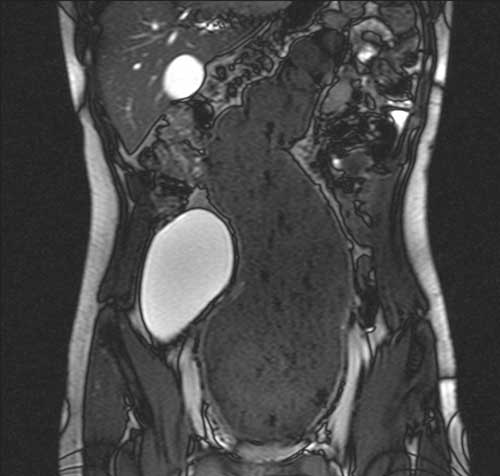

Passano 3 settimane... di nuovo turno di Pronto Soccorso e... giunge nuovamente L.! Troviamo il ragazzo in attesa nel corridoio sdraiato su una barella, visibilmente sofferente e debilitato. Lo facciamo entrare subito: L. ci racconta che dall�ultima volta che ci siamo visti il dolore addominale � sempre stato presente e le scariche diarroiche, negli ultimi giorni, sono addirittura aumentate di frequenza, raggiungendo 25 scariche al giorno! Recentemente, inoltre, � comparsa astenia, disappetenza e, rispetto al precedente controllo, una riduzione del peso di 6 kg.�...Qualcosa non quadra... ripensiamo ai nostri sospetti diagnostici: esclusa la �banale� gastroenterite, consideriamo anche difficile che il quadro possa essere giustificato interamente da un disturbo psico-somatico. Visitiamo L.: l�addome � piano e trattabile ma, questa volta, alla palpazione si apprezza una massa di consistenza dura, di circa 10 x 20 cm, localizzata in sede pelvica con impegno meso-epigastrico. La peristalsi � torbida. Richiediamo un�ecografia addominale. Dopo pochi minuti l�ecografista ci contatta per suggerirci una RM dell�addome, viste le difficolt� nell�eseguire l�ecografia. Questa mostra una marcata dilatazione di tutto il retto e del sigma (diametro massimo di circa 12 cm di calibro a livello del retto), ma con spessore di parete nei limiti; il lume risulta occupato da abbondante materiale poltaceo e gas (Figura 1). La vescica � completamente dislocata in fossa iliaca destra con morfologia allungata. Rimaniamo stupiti dalle immagini radiologiche e iniziamo ad ipotizzare la possibile causa in relazione alla clinica ed al reperto della RM: patologia ostruttiva? Megacolon tossico? Massa fecaloide?

Figura 1. RM: dilatazione retto-sigma (dm max ≈ 12 cm), pareti nei limiti, materiale poltaceo e gas, vescica in FID.